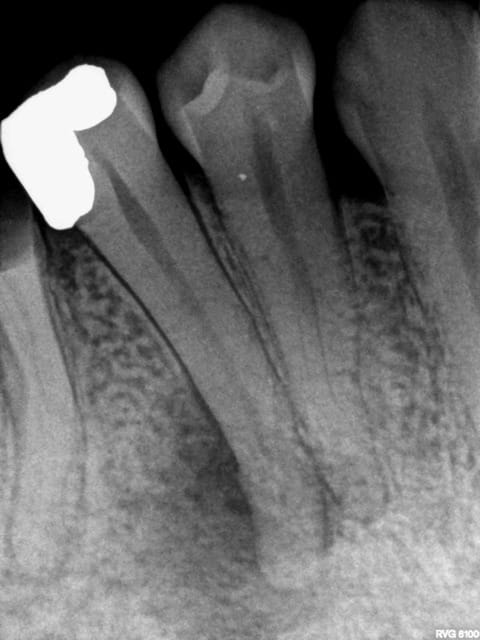

Pour l'instant je me contente de faire en sorte que les patients soient bien remboursés c'est pas forcément tout le temps l'indication clinique ( quoique ici ca l'était) mais ca va faire hurler les adeptes du no post no crown ( je me demande d'ailleurs comment il font pour faire accepter leurs devis avec notre nomenclature de merde).

Ici par exemple ic à 200 % ( mut ss 200 %) Et ceram à 400 %. Seul reste à charge 107,5 euros sur la molaire qui est remboursée à 300 % ( dents postérieures)

Les provisoires sont offertes -)))

Ca reste effectivement une dentisterie agricole.

une heure de rdv de a à z. Ca amortit la perte de temps des endos.

Les radios initiales quand meme. Pour les adeptes des soins conservateurs opposables. -))))

Pas la peine d'inventer de la prothèse elle est servie sur un plateau. -))))